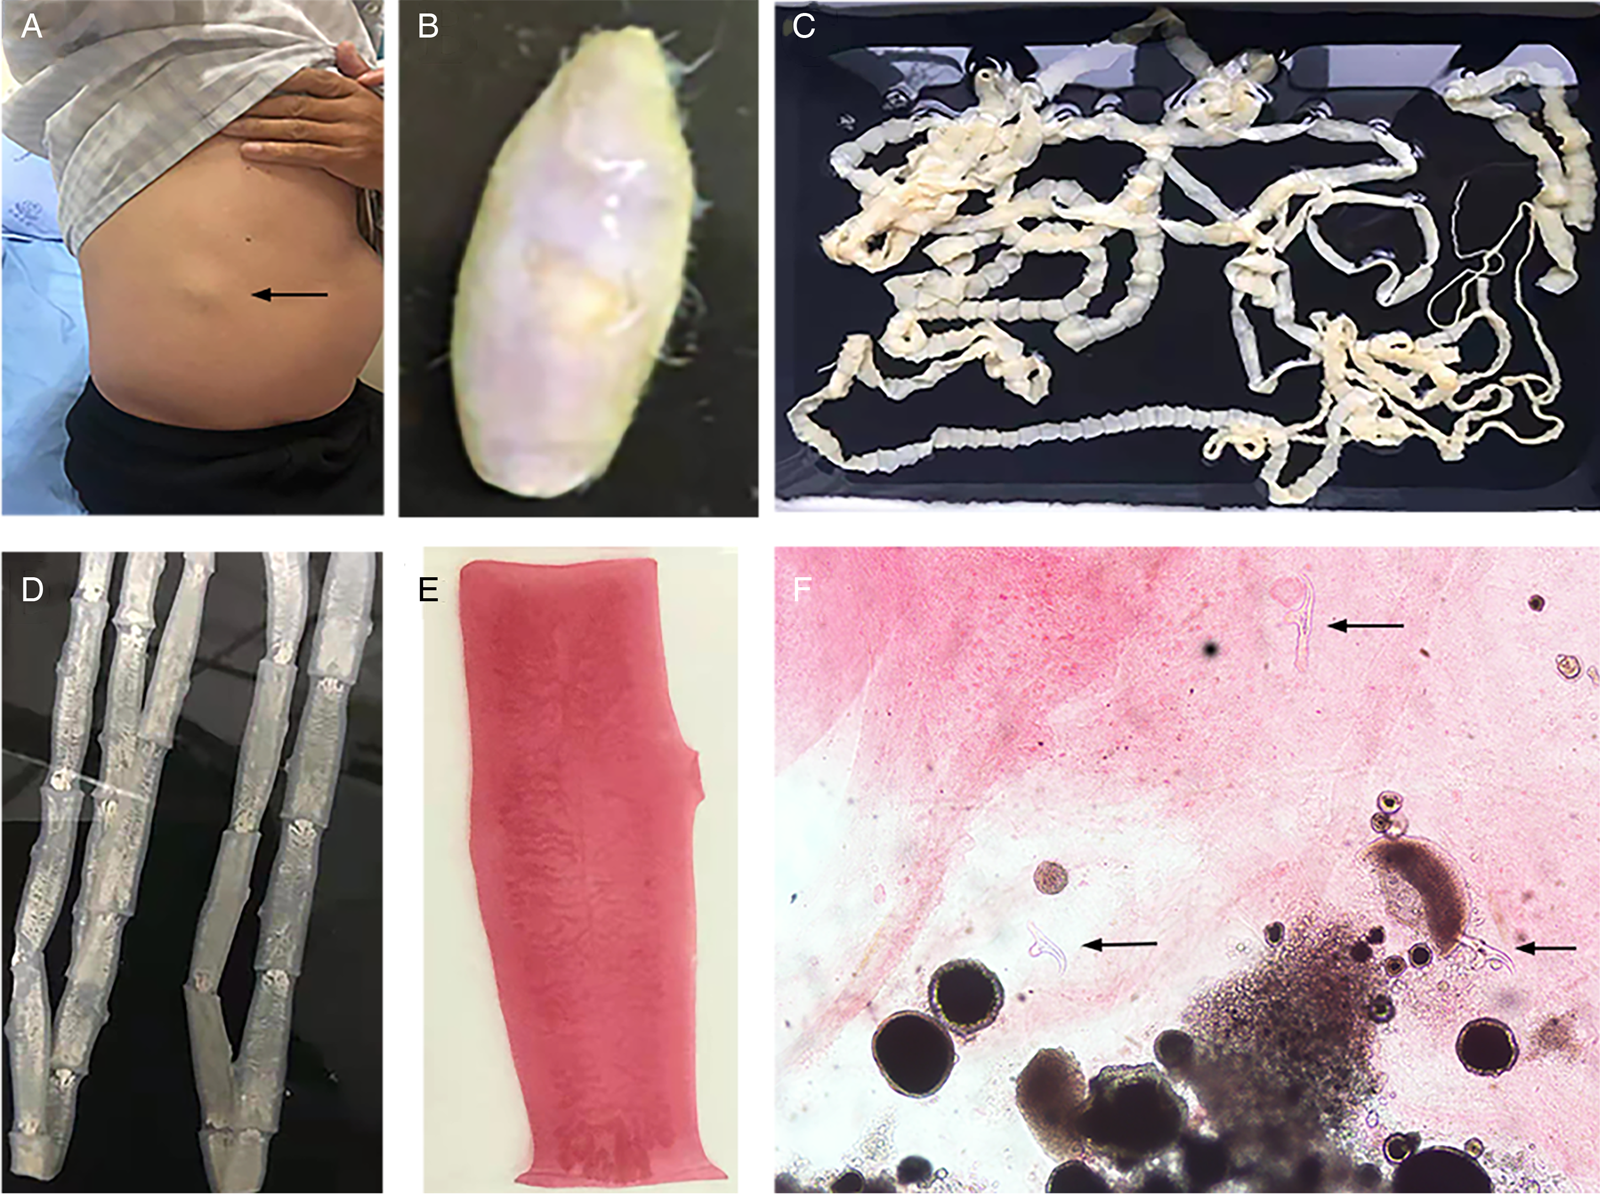

The routine laboratory blood tests, including eosinophil and lymphocyte count, were completely normal apart from the elevated inflammation markers (C-reactive protein and neutrophil count). Schistosomes, Clonorchis sinensis, Echinococcus granulosus and Toxoplasma gondii antibodies were negative in his serum, as were Cryptococcus capsular antigen and next-generation sequencing results from cerebrospinal fluid. Multiple intracranial nodules affecting the supratentorial and infratentorial cerebral parenchyma were shown in detail on CT and MRI of the head, indicating possible intracranial parasitic infection (Fig. 1). Ultrasound scan confirmed the presence of 2 palpable and soft masses located in muscles, which were approximately 19 × 8 × 15 mm3 under the right chest wall and 26 × 10 × 19 mm3 under the right midaxillary line (Fig. 2). A subsequent biopsy of the mass (Fig. 3) showed larval-like tissue, peripheral fibrous tissue hyperplasia, lymphocytic infiltration and hyaline degeneration. The patient was probably diagnosed with taeniasis and cysticercosis and treated with oral albendazole (400 mg, twice daily) over 2 weeks. Hydrocortisone 50 mg was provided 2 days after the first albendazole treatment to counteract any potential negative effects on the central nervous system. After only 2 days of this antiparasitic treatment, the adult tapeworm was eliminated through the patient's feces (Fig. 3). When compared with the first MRI (half a month before antiparasitic treatment), the second MRI (half a month after antiparasitic treatment) demonstrated a slightly smaller focus (Fig. 1). The headache and vomiting resolved, and the patient remained symptom free over a 3-month follow-up period.

Fig. 3. Tapeworm materials from the patient: (A) subcutaneous mass; (B) cyst; (C) adult tapeworm; (D) unstained proglottids; (E) a stained proglottid and (F) cystic lesion with hydrochloric acid-carmine staining showing presumed deciduous hooks (black arrows).

The adult tapeworm was milky white, flat and long like a belt, thin and translucent, and the main segments are shown in Fig. 3. The uterine branches in the gravid proglottids were regular, and each side had approximately 15–30 branches (Fig. 3). The slide of the cyst showed no obvious typical features; however, some presumed deciduous hooks were found in the same slide, leading to indistinguishable morphology (Fig. 3).

Three common Taenia species can be differentiated by examination of their morphological characteristics, such as the scolex, mature and gravid proglottids in the adult stage, and the scolex in the larval stage (Eom et al., Reference Eom, Rim and Jeon2020). However, the differential diagnosis between them is challenging when their morphology is not so typically visible. As far as morphological characteristics were concerned, the gravid proglottids (Fig. 3) from this patient were the same as T. saginata or T. asiatica, not T. solium, while the morphological evaluation of cysticercosis, that showed the presence of detached hooks (Fig. 3), referred to T. asiatica and T. solium rather than T. saginata. However, the traditional morphological taxonomy has some inherent limitations leading to possible false-species identification and can neglect cryptic or pseudocryptic species. That is the reason why integrated taxonomy approaches, wherein molecular studies combine detailed morphological information, are important in helping characterize pairing at the individual level resulting in the perfect characterization of cryptic biodiversity (Hebert et al., Reference Hebert, Cywinska, Ball and deWaard2003; Laakmann et al., Reference Laakmann, Blanco-Bercial and Cornils2020).